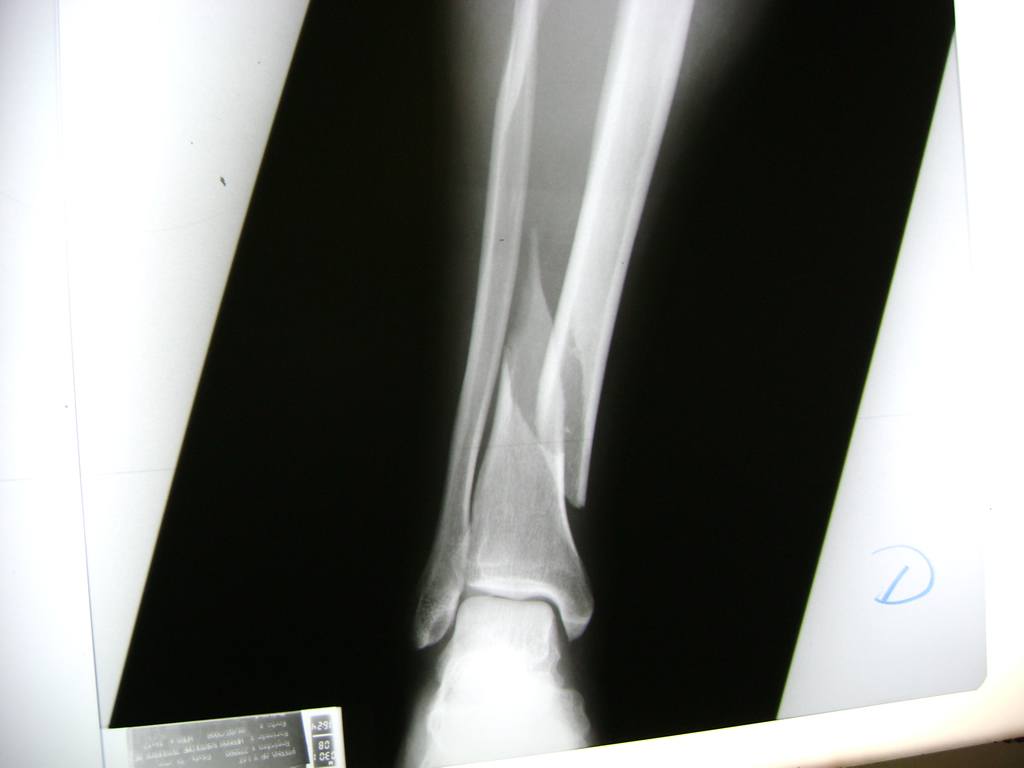

Cirugías de Codos - Perone y Tibia

Aunque cada uno de estos huesos puede fracturarse por separado, normalmente la rotura es una lesión que se produce de forma conjunta

La mayor parte de las roturas implican a la parte proximal del hueso (parte del hueso próximo a la rodilla) o a la parte distal (parte del hueso cerca del tobillo).

Debido a la fina cobertura de piel que recubre la tibia y el peroné, las fracturas generalmente son abiertas, es decir, el hueso roto rasga la piel, atravesándola. Las fracturas de tibia y peroné generalmente se producen por un fuerte impacto o torsión.